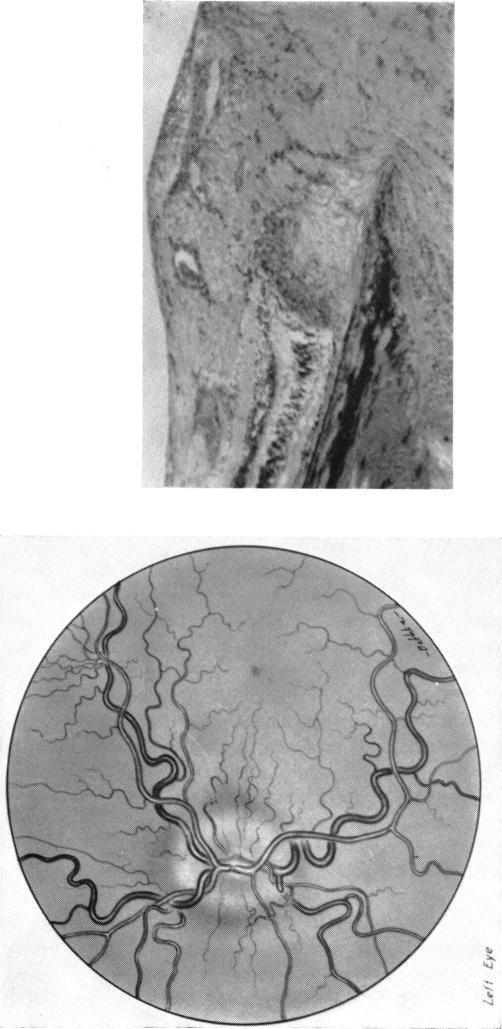

THE EYE AND CYSTIC FIBROSIS OF THE PANCREAS: A R'ESUM'E.

Trans Am Ophthalmol Soc. 1964;62:123-39.